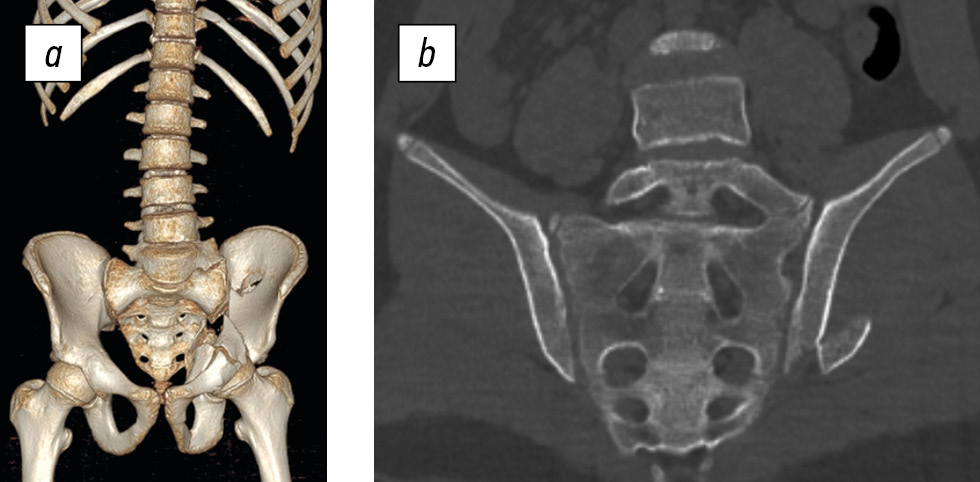

Fig. 2. Three-dimensional reconstruction (a) and CT scan (b) of the lower lumbar spine and sacrum of a 16-year-old female patient. Type a sacral injury (right iliac wing fracture). Transitional lumbosacral vertebra, type III, subtype b.

Analysis of the CT scans shown in Fig. 2 focused on the sacrum, which exhibits five pairs of sacral foramina. Normally, five sacral vertebrae fuse by the age of 22–24 years to form the sacrum (os sacrum), which has four pairs of sacral foramina [12]. A sacrum with five pairs of sacral foramina, as revealed by 3D reconstruction, is an indicator of transitional vertebrae type III or IV [11].